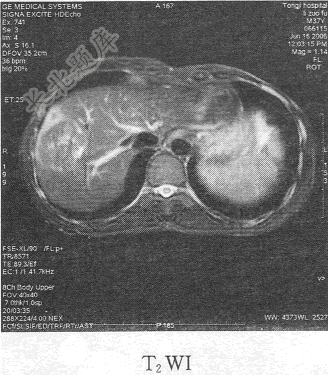

- 单项选择题患者男,54岁。体检发现肝脏占位,MR图像如下,最有可能的诊断是

C、肝血管瘤